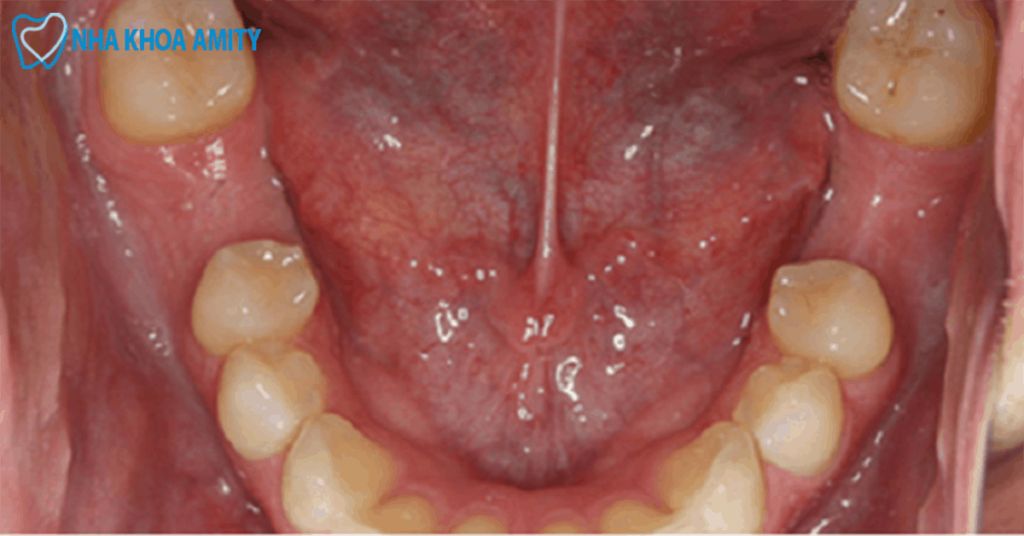

Răng nanh (răng số 4), răng số 6, 7 đều là những răng vĩnh viễn giữ vai trò quan trọng trong chức năng nhai. Và có ảnh hưởng trục tiếp đến hệ thần kinh đặc biệt là răng số 6, 7. Nếu không được thực hiện nhổ đúng quy trình thì có thể gây nên biến chứng nguy hiểm. Vì vậy, khi có chỉ định nhổ răng nanh, răng số 6,7, bạn cần lưu ý trong lựa chọn địa chỉ uy tín có đội ngũ bác sĩ giỏi chuyên môn, giàu kinh nghiệm. Hệ thống cơ sở vật chất trang thiết bị hiện đại, quy trình thực hiện đảm bảo vệ sinh, an toàn và ít đau.

Răng cấm hay răng số 6 là răng vĩnh viễn và chỉ mọc một lần duy nhất trong đời. Răng này thường bắt đầu xuất hiện trên cung hàm khi 6-7 tuổi. Trong nha khoa, việc bảo tồn răng luôn được ưu tiên hàng đầu trong đó bao gồm răng cấm. Bởi những chiếc răng tự nhiên vẫn luôn là những chiếc răng có chất lượng tốt nhất. Tuy nhiên, răng cấm với vai trò chính trong ăn nhai lại dễ gặp phải các vấn đề như viêm nhiễm, sâu, hỏng răng. Vậy có nên nhổ răng cấm không?

Rấm được chỉ định nhổ trong trường hợp răng bị sâu quá nặng không thể điều trị bảo tổn răng, gây hủy hoại tủy. Hoặc do chấn thương không thể phục hình được và khi thay răng sữa. Với những trường hợp có thể bảo tồn nên ưu tiên thực hiện các biện pháp chỉnh nha bảo tồn răng, hạn chế nhổ răng cấm.